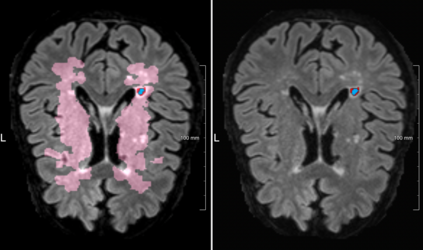

Lacunes of presumed vascular origin are fluid-filled cavities of between 3 - 15 mm in diameter, visible on T1 and FLAIR brain MRI. Quantification of lacunes relies on manual annotation or semi-automatic / interactive approaches; and almost no automatic methods exist for this task. In this work, we present a two-stage approach to segment lacunes of presumed vascular origin: (1) detection with Mask R-CNN followed by (2) segmentation with a U-Net CNN. Data originates from Task 3 of the "Where is VALDO?" challenge and consists of 40 training subjects. We report the mean DICE on the training set of 0.83 and on the validation set of 0.84. Source code is available at: https://github.com/hjkuijf/MixLacune . The docker container hjkuijf/mixlacune can be pulled from https://hub.docker.com/r/hjkuijf/mixlacune .